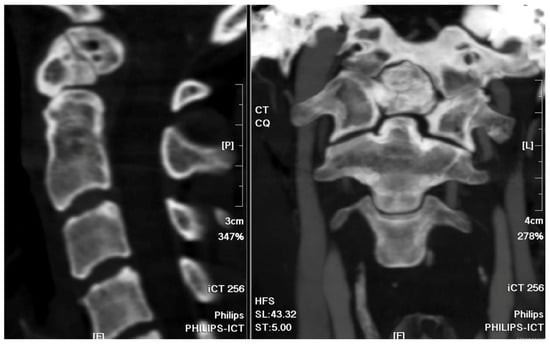

For the atlantoaxial subluxation, the patient was prepared for the AR-assisted navigational instrumentation surgery. Preoperative cervical spinal MRI and computed tomography angiography (CTA) were performed to rule out angioarchitecture variation. Post-surgery, the patient exhibited a notable alleviation of her symptoms. Postoperative recovery was uneventful and without neurological deficit, culminating in her discharge on the fourth postoperative day.

Preoperatively acquired cervical spinal MRI and CTA data were incorporated into the BrainLab Curve stereotactic neuro-navigation system (BrainLab AG, Munich, Germany). Prior to the procedure, we delineated the bilateral VAs and bony anatomy in distinct colors on a 3D-reconstruction derived from the preoperative CTA. At the surgery’s onset, the patient was secured in a prone position using a skull clamp. A navigation recognition reference cluster was affixed to the head frame for system registration. Subsequent to this, another stereotactic reference was attached to the KINEVO 900 microscope (Carl Zeiss AG, Oberkochen, Germany). An initial intraoperative CT scan was executed, and its imagery was coalesced with the pre-configured navigation images to counteract potential inaccuracies stemming from divergent scan positioning. For the C1-C2 fixation, we determined screw entry points and trajectories utilizing the navigation system, adopting a posterior midline technique. Initially, the lateral facet of the C1 posterior arch was unveiled to discern bilateral–lateral masses. Subsequent exposure included the spinous process, laminae, and the medial segments of C2 lateral masses. Utilizing the AR modality, the bilateral VAs, distinctly marked in red, were distinctly observed under the microscope. Concurrently, projections of the supplementary osseous structure were cast onto the operative field (Figure 4). Subsequently, entry points and trajectories for the C2 pedicular screws were orchestrated using real-time navigation in sync with the microscope-integrated AR system (Figure 5). Upon appropriate magnification and zooming out, the surgeon could clearly visualize the anatomical structures, avoiding any obstruction caused by surgical tools. Validation using AR navigation and intraoperative fluoroscopy confirmed the correct positioning. We proceeded by creating a pilot hole with a 2 mm high-speed burr. Following the pilot hole, we used a tool equipped with a navigator to ensure adequate bone purchase and a safe trajectory for further tapering. Finally, we placed poly-axial C2 pedicular screws (3.5 × 28 mm) along the pre-established trajectory, ensuring no breaches or vascular injuries. A corresponding navigation strategy was employed for the bilateral C1 lateral mass screws (3.5 × 30 mm). Post screw placement, an intraoperative CT scan affirmed the screw alignments (Figure 6). Succeeding surgical phases, encompassing the C1 laminectomy and rod application adhered to conventional protocols.

Figure 2. Cervical spine CT bone window images. The sagittal view and coronal view revealed the non-fused C2 bony elements of the odontoid process.

Figure 6. Intraoperative CT for screw validation. (a) Sagittal view; (b) coronal view; (c) axial view at C1 level; (d) reconstruction of 3D image.